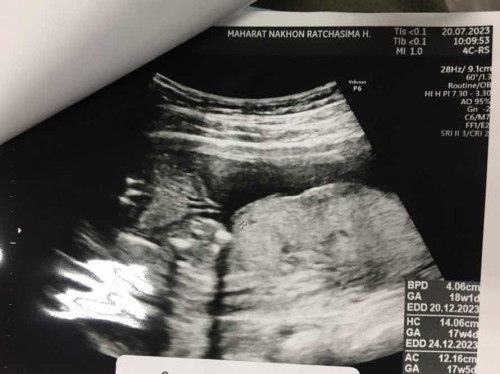

หนูมองไม่ออกค่ะเเม่ หมอบอกผู้ชาย เเต่คนรู้จะกตรวจที่เดียวกันบอกผู้ชายออกมาเป็นผู้หญิง